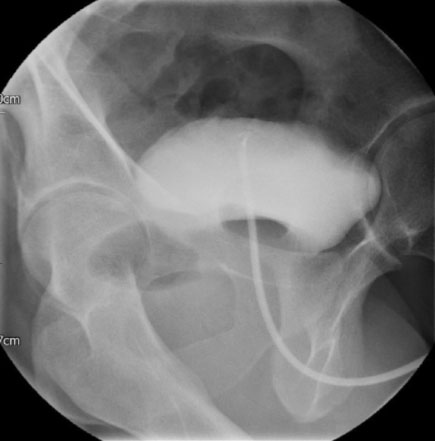

Figure 6: Cystogram demonstrating no urinary leak (Lateral view).

Share Image:

Unfortunately, due to a long waiting list for radiological procedures, the patient had a cystography a month later. No evidence of urinary leak was demonstrated (Figure 5 and Figure 6). The urethral catheter was eventually removed and he was able to pass urine adequately. A post-void bladder scan showed only 75 mL.